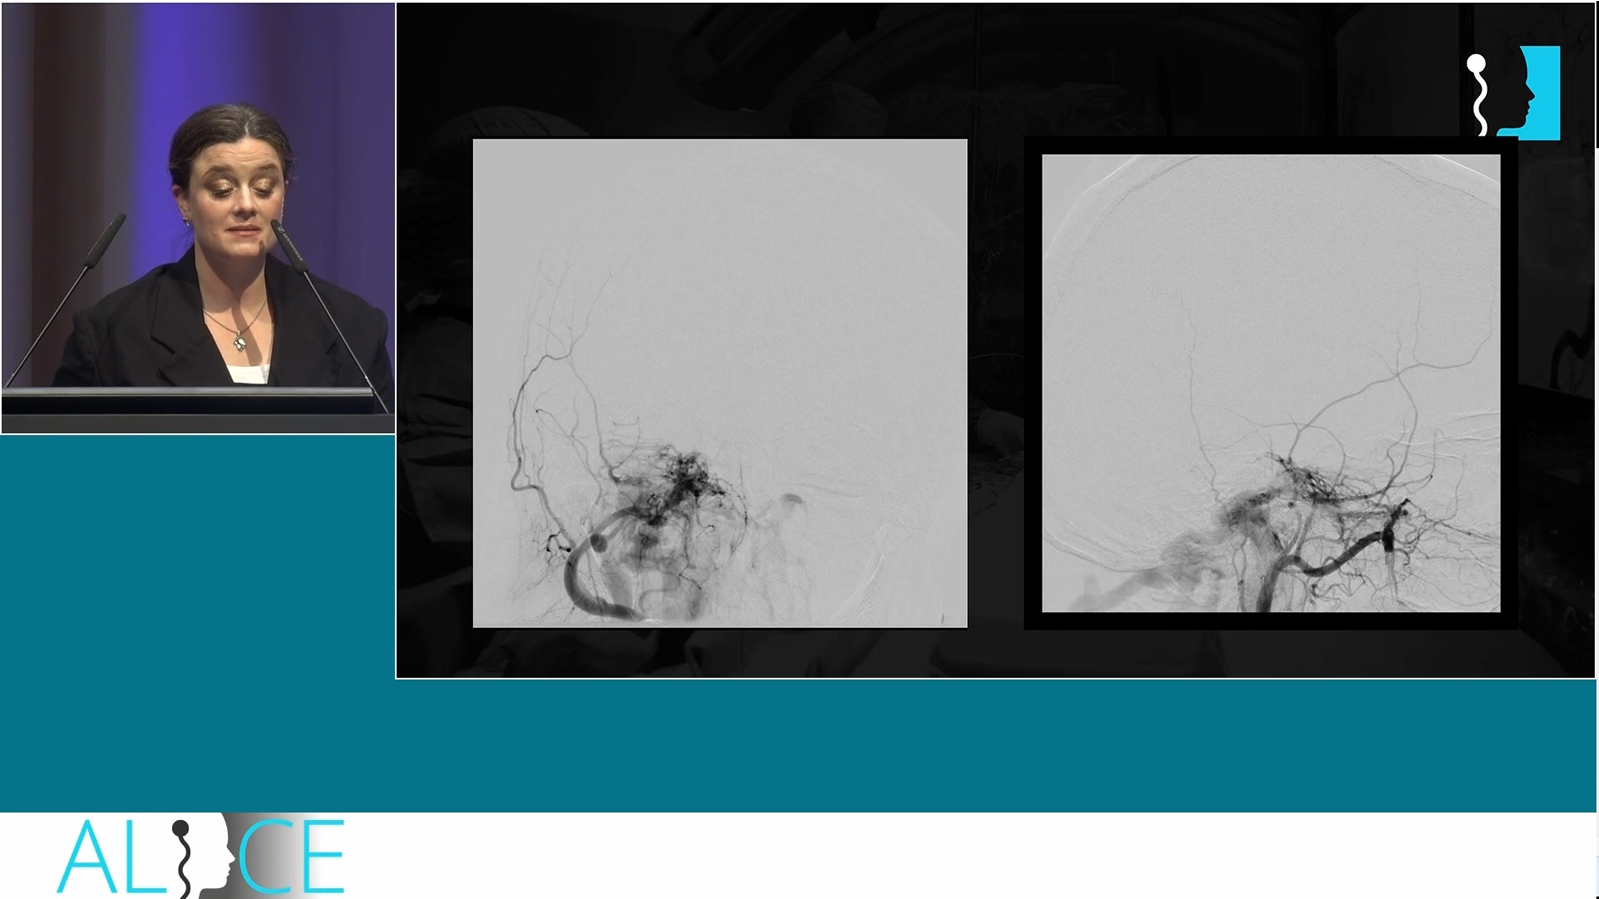

Occipital AVM treated by transarterial pressure cooker embolization

Watch the video